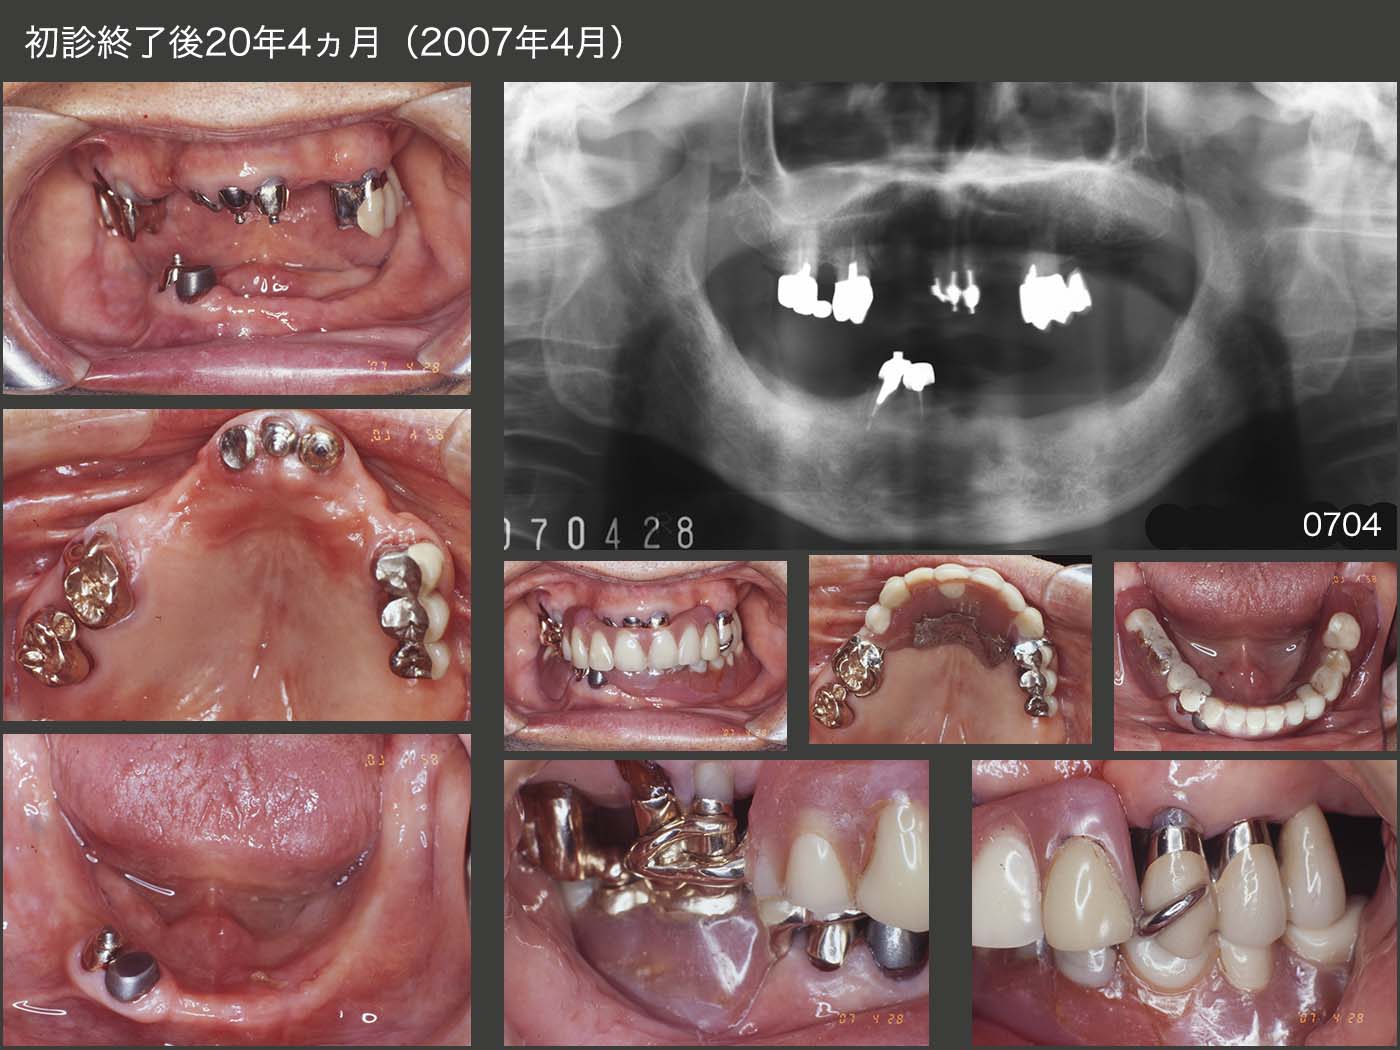

2007年4月,初診終了後20年4か月の状態である.スライド10〜12で考察するが,この間,合計7本の歯を失った.また,右上1,2および左上1に歯冠破折が生じた.96年,上顎に義歯を新製した.

02年に脳梗塞を患い,何とか5年間,片道2時間以上かけて通院して頂いていたが,07年4月以降通院不可能となり,08年他界された.

上顎において,この20年4ヵ月の変化は,スライドに記載してあるとおりである.すなわち,下顎に対合歯のある主に前歯部にトラブルが発生していることが分かる.最終的には,歯冠破折で残根状としたりあるいは歯根破折で抜歯となったが,その前に,何度かコンポジットレジン修復を施したり,再合着を繰り返してきた.